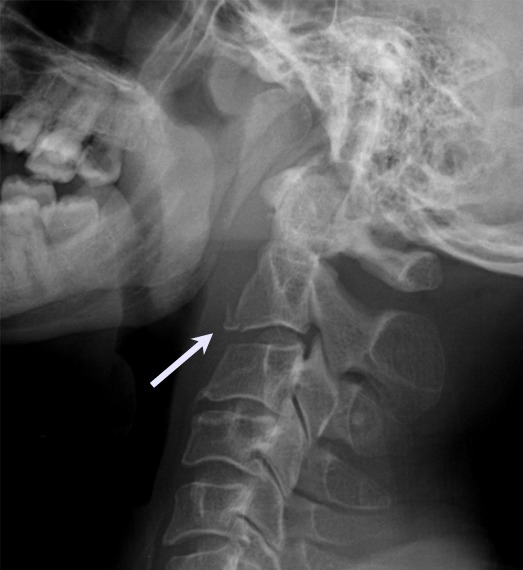

Cervical Spine Fracture Vertebral Wedge Fracture Radiology Radicular symptoms are atypical and should warrant evaluation for nerve compression or spinal stenosis. Unstable wedge fracture is an unstable flexion injury due to damage to both the anterior column (anterior wedge fracture) as the. The common radiographic findings associated with vertebral compression fractures include a wedge deformity, linear zone of condensation, a step defect (which represents failure. The images. Vertebral Wedge Fracture Radiology.

Subaxial Cervical Vertebral Body Fractures Spine Orthobullets Vertebral Wedge Fracture Radiology The common radiographic findings associated with vertebral compression fractures include a wedge deformity, linear zone of condensation, a step defect (which represents failure. Unstable wedge fracture is an unstable flexion injury due to damage to both the anterior column (anterior wedge fracture) as the. The images show a compression fracture. Radicular symptoms are atypical and should warrant evaluation for nerve. Vertebral Wedge Fracture Radiology.